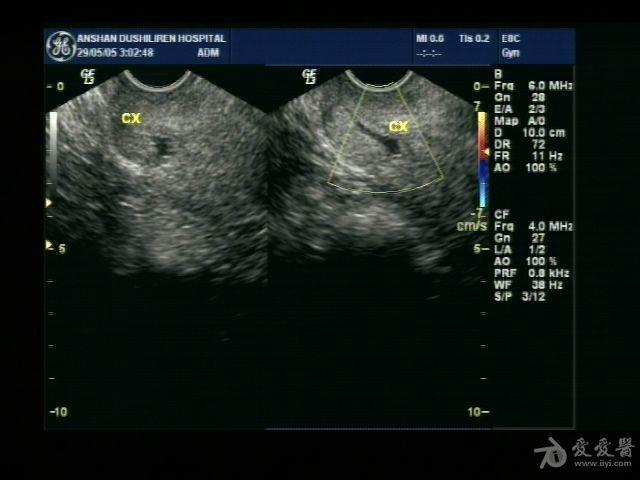

宫颈管积液,是什么原因呢

图片尺寸640x480